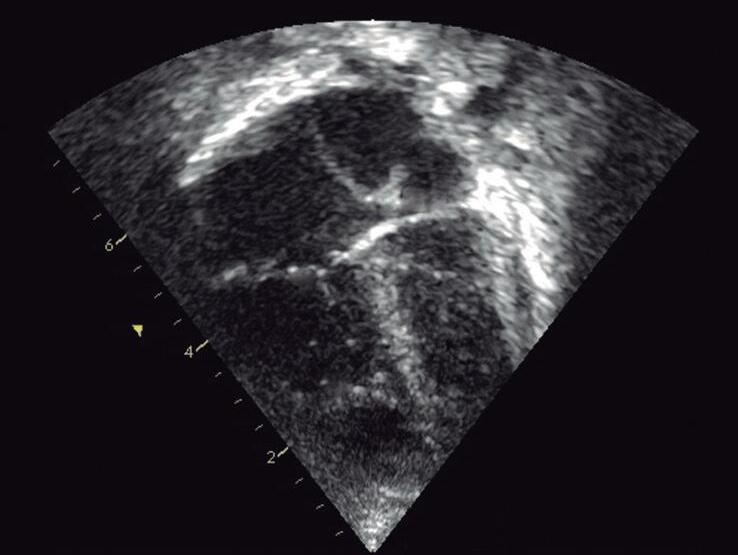

Para obter o plano paraesternal eixo curto, “rodamos” o transdutor no sentido horário com o index apontando para o ombro esquerdo do paciente (▶ Vídeos 1-17 e 1-18). A visão eixo curto das grandes artérias consiste em valva aórtica (posicionada no centro da imagem), via de saída do VD (região infundibulovalvar do VD e artéria pulmonar), valva tricúspide e átrios (Fig. 1-7a e ▶ Vídeo 1-19). Movimentando o transdutor no sentido craniocaudal também é possível obtermos o eixo curto dos ventrículos ao nível dos músculos papilares e da valva mitral para a análise da contratilidade ventricular, do septo interventricular muscular e da valva mitral (Figs. 1-5b e 1-7b, c; ▶ Vídeos 1-17, 1-18, 1-20 e 1-21). O mapeamento em cores é importante para pesquisa de comunicação interventricular muscular e disfunção valvar mitral (Fig. 1-7).

Fig. 1-7. Plano paraesternal eixo curto com Doppler colorido: grandes artérias (a), eixo curto dos ventrículos ao nível dos músculos papilares (b) e da valva mitral (c). AD: átrio direito; AE: átrio esquerdo; VD: ventrículo direito; Ao: aorta; AP: artéria pulmonar; VT; valva tricúspide; VP: valva pulmonar; VE: ventrículo esquerdo; S: septo interventricular; mp: músculo papilar; VM: valva mitral.